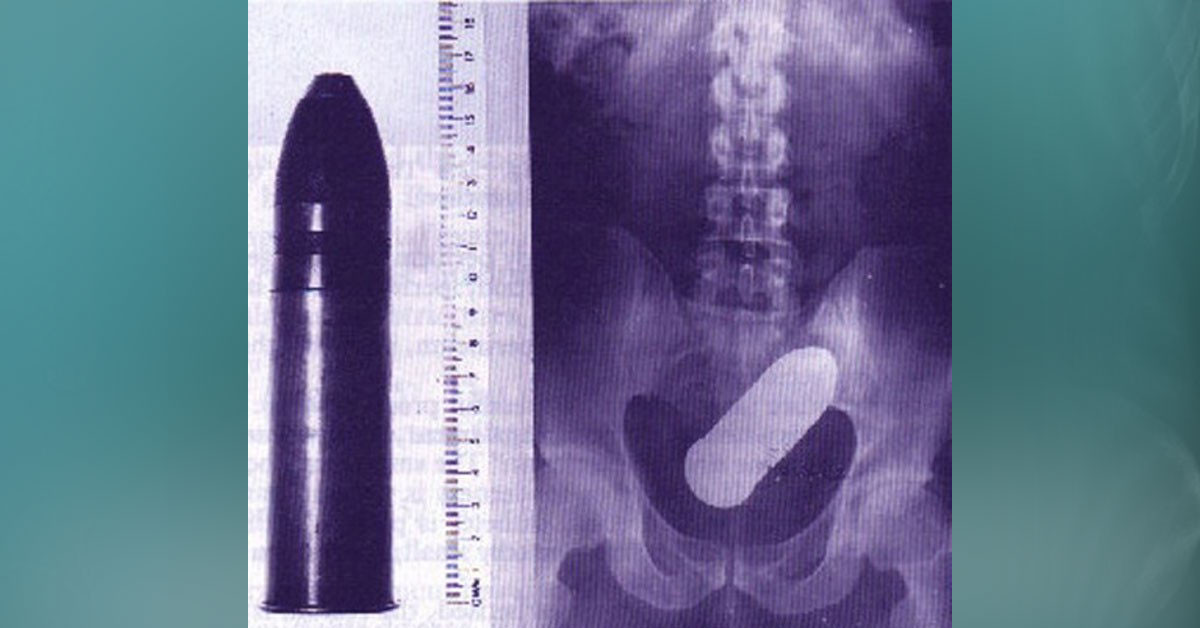

Bu da bir başka olay... Soda şişesine oturunca ölümle burun buruna geldi.